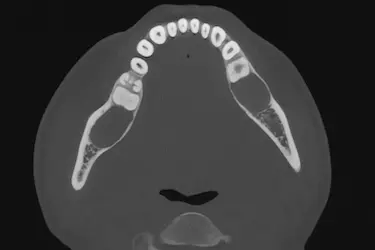

TAC dental , que significa Tomografía Axial Computerizada, es una prueba de imagen diagnóstica destinada a tomar imágenes tridimensionales de los dientes, las estructuras nerviosas y los huesos craneofaciales de una persona.

La principal ventaja de hacerse un TAC dental 3D es que permite a nuestros especialistas realizar cortes bidimensionales y tridimensionales de las imágenes obtenidas de tu boca.

Con las fotos de un TAC dental se pueden ver imágenes detalladas de los dientes, huesos maxilares, mandíbula, raíces dentales y tejidos de alrededor, permitiendo un diagnóstico preciso.

TAC del maxilar superior

El TAC maxilofacial se enfoca en la parte superior de la boca, evaluando el maxilar superior, donde se encuentran los dientes superiores, el paladar y los senos maxilares.

Gracias a este estudio podemos valorar con detalle la altura y el espesor del hueso en la zona posterior, algo esencial antes de colocar implantes o realizar una elevación de seno maxilar.

TAC completo de ambas arcadas

Proporciona una imagen 3D completa de las dos arcadas, maxilar superior e inferior, junto con los tejidos y estructuras óseas adyacentes.

Este examen ofrece una visión global de toda la cavidad oral, facilitando la planificación integral de tratamientos que combinan prótesis, ortodoncia o implantes en ambas arcadas.